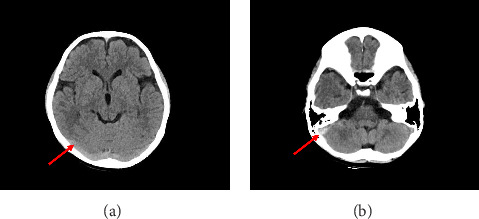

脑静脉窦血栓形成(CVST)在儿童中很少见(占儿童卒中的0.5%-1.0%),与闭合性创伤性脑损伤相关的病例很少。一名七岁女孩在轻度闭合性颅脑损伤后出现神经系统症状。早期CT影像显示了最初被忽视的细微发现,导致诊断延迟。随后的磁共振成像(MRI)和磁共振静脉造影(MRV)证实了CVST的诊断。患者成功地接受依诺肝素桥接治疗,随后接受利伐沙班治疗,实现血栓完全溶解,无出血并发症。本病例强调了儿童创伤后CVST的诊断挑战,其中最初的影像学征象可能被忽视。该研究强调了在持续症状的儿童脑外伤中警惕成像解释的重要性,并证明了新型口服抗凝剂(NOACs),特别是利伐沙班,作为这一人群的治疗选择的有效性和安全性。

Cerebral venous sinus thrombosis (CVST) is rare in children (0.5%-1.0% of pediatric strokes) and uncommonly associated with closed traumatic brain injury. A 7-year-old girl presented with neurological symptoms following a mild closed craniocerebral injury. Early CT imaging revealed subtle findings that were initially overlooked, leading to delayed diagnosis. Subsequent magnetic resonance imaging (MRI) and magnetic resonance venography (MRV) confirmed the diagnosis of CVST. The patient was successfully treated with enoxaparin bridging followed by rivaroxaban, achieving complete thrombus resolution without bleeding complications. This case highlights the diagnostic challenge of posttraumatic CVST in children, where initial imaging signs may be overlooked. It underscores the importance of vigilant imaging interpretation in pediatric brain trauma with persistent symptoms and demonstrates the efficacy and safety of novel oral anticoagulants (NOACs), specifically rivaroxaban, as a therapeutic option in this population.